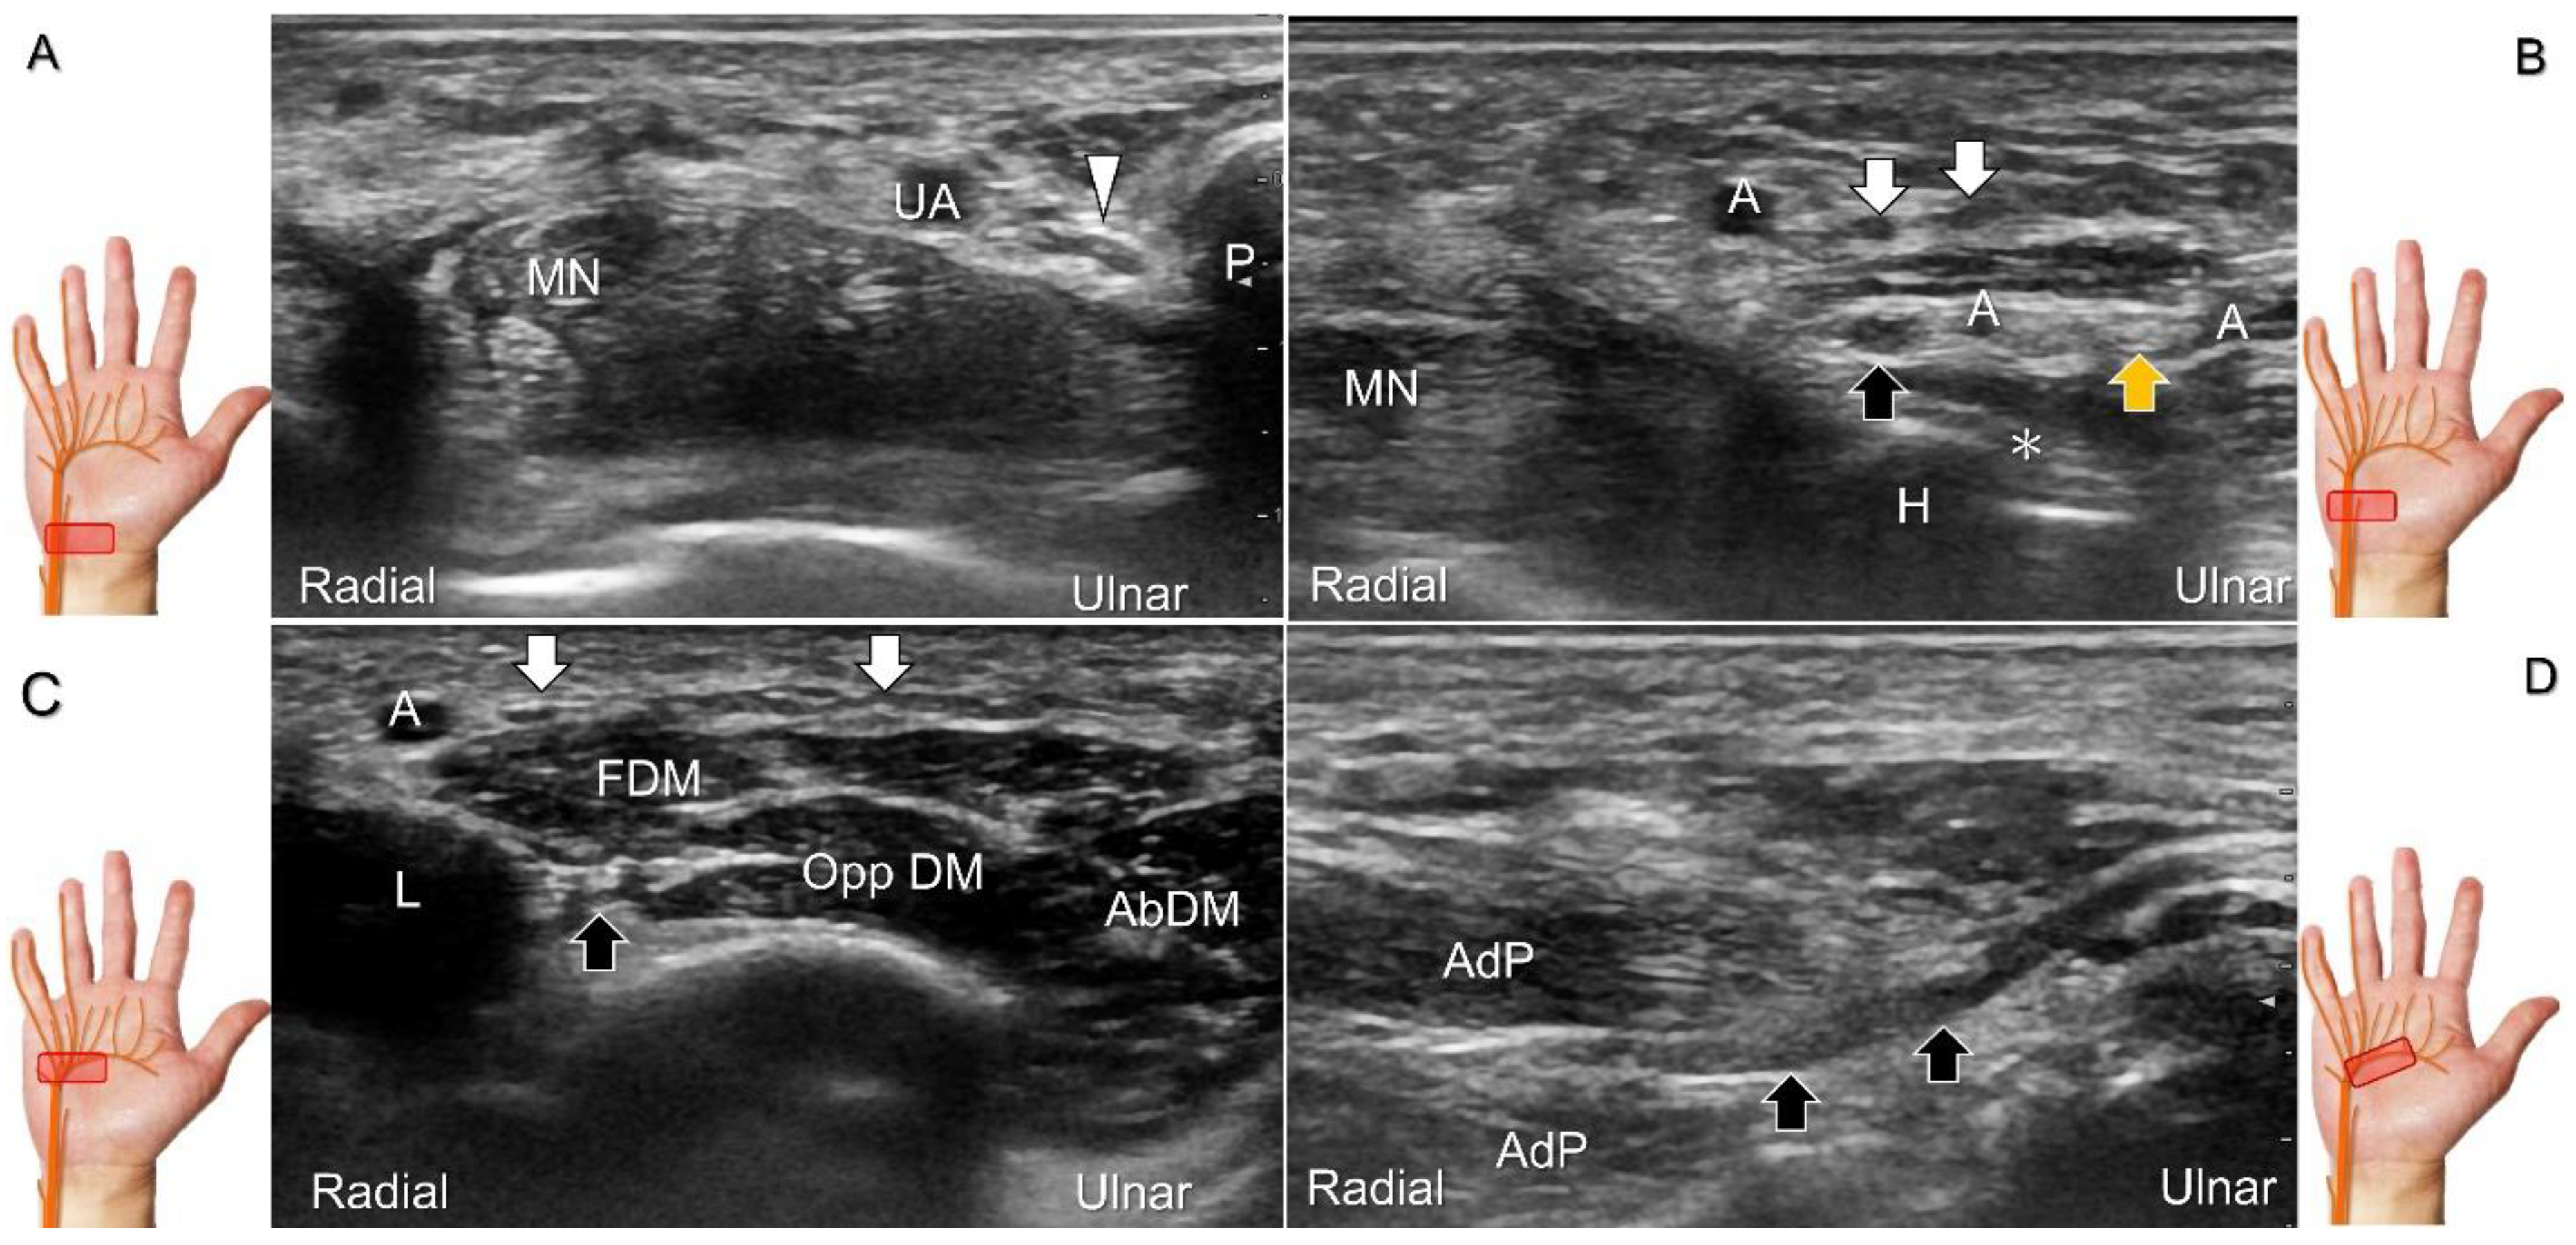

Figure 13. Sonographic imaging (short-axis view) shows the ulnar nerve within the Guyon’s canal (A), separation of branches beside the pisohamate hiatus (B), deep branch of the ulnar nerve located between the hypothenar muscles distal to the hook of the hamate (C). Long-axis view (through pivoting the transducer) shows the segment of the deep branch within the adductor pollicis muscle (D). Arrowhead: ulnar nerve; white arrows: superficial branch of the ulnar nerve; black arrows: deep branch of the ulnar nerve; orange arrow: branch of the ulnar nerve to the abductor digiti minimi; *: pisohamate ligment MN: median nerve; UA: ulnar artery; P: pisiform; H: hook of hamate; A: artery; L: lumbrical muscle; FDM: flexor digiti minimi brevis muscle; Opp DM: opponens digiti minimi muscle; AbDM: abductor digiti minimi muscle; AdP: adductor pollicis muscle.

Scanning Technique

To locate the Guyon’s canal, the transducer is placed along the axial plane on the volar wrist with the forearm supinated. This will reveal the ulnar nerve and artery within the canal (Figure 13A). To investigate the nerve’s long axis, the transducer is rotated 90 degrees. By moving the transducer toward the finger, the superficial and deep branches can be seen. Between the pisiform and hamate, the superficial and deep branches (along with their accompanying vessels) can be visualized as separated by the fibrous arch of hypothenar muscles, respectively (Figure 13B) [39].

The superficial branch divides into two palmar digital nerves. They run superficially along the little finger and half of the ring finger. The deep branch, on the other hand, can be observed between the flexor digiti minimi brevis and opponens digiti minimi muscles before it penetrates the deep aspect of the palm (Figure 13C). By pivoting the transducer, the physician can display the long axis of the deep branch, extending all the way to the segment within the adductor pollicis muscle (Figure 13D).